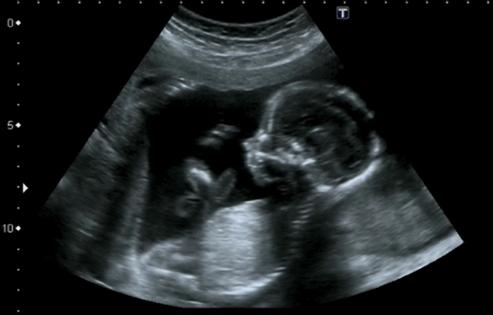

A Denver company has received federal approval to market an artificial intelligence program it says can predict when babies will arrive based on their ultrasounds, raising the possibility of flagging premature births.

Delivery Date AI predicts when a baby will be born, with an 11-day margin of error in either direction, based on second- and third-trimester ultrasounds.

The AI was trained on millions of ultrasound images from the University of Kentucky that had information about how long the pregnancy lasted, with the patients’ personal data removed.